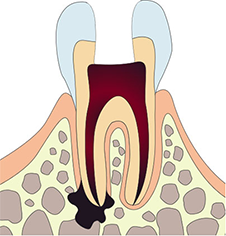

심한 우식증으로 치수까지 감염이 되거나 치아의 파절 등

외상으로 치수가 노출되면 감염이나 염증이 발생합니다.

신경치료(근관치료)는 치수까지 깊게 진행되어 치수염, 근단치주염 등 치수 주위 조직에 염증이 생겼을 때 시행하는 치료입니다.

심한충치

충치가 신경까지 깊게 진행된 상태

주요 증상

- 지속적인 통증

- 씹을 때 아픔

- 잇몸 부종

치수염

치아 내부 신경에 염증이 생긴 상태

- 극심한 자발적 통증

- 밤에 더 심한 통증

- 뜨거운 것에 아픔

뿌리끝병소

치근 끝 부위에 염증이나 낭종이 생긴 상태